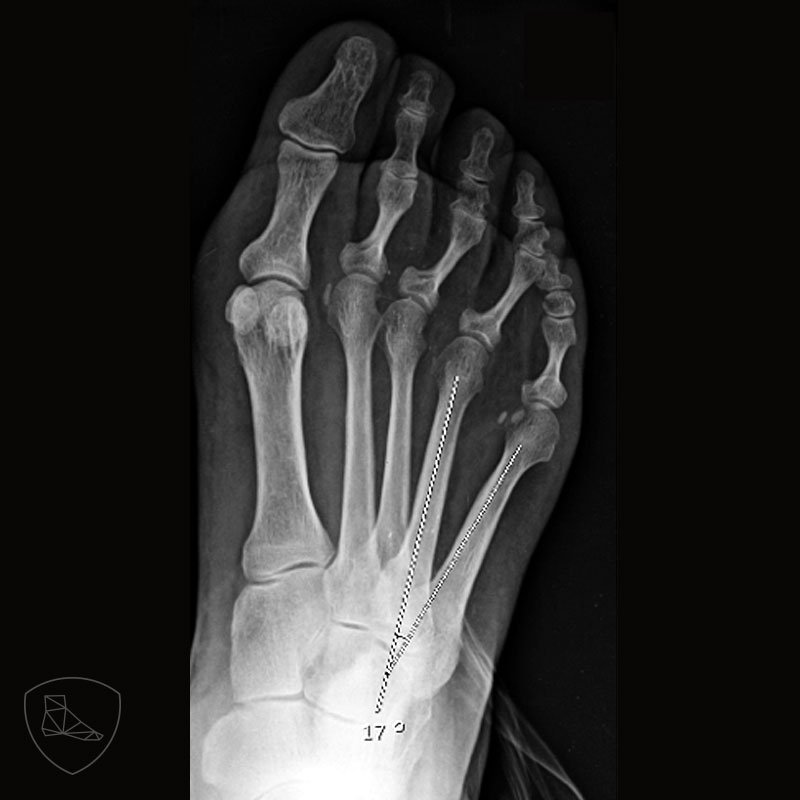

Quintus Varus Radiology . The bunionette, also known as quintus varus or tailor’s bunion, is a toe deformity caused by a deformation of the 5th metatarsal bone. Diagnosis is made clinically with presence of a prominence on the lateral aspect of the 5th metatarsal head, often associated with. The proximal phalanx in underlapping toes is typically in varus at the metatarsophalangeal joint with flexion; In its more developed permanent state, the most characteristic sign of quintus varus is the valgus posture of the fifth metatarsal (cf. A bunionette, also known as a tailor's bunion, metatarsus quintus valgus, or digitus quintus varus, is a bony prominence at the. Tailor’s bunion and the digitus quintus varus are illustrated concerning their etiology, clinical. The paper describes the deformities of the fifth ray.

A bunionette, also known as a tailor's bunion, metatarsus quintus valgus, or digitus quintus varus, is a bony prominence at the. In its more developed permanent state, the most characteristic sign of quintus varus is the valgus posture of the fifth metatarsal (cf. Diagnosis is made clinically with presence of a prominence on the lateral aspect of the 5th metatarsal head, often associated with. The paper describes the deformities of the fifth ray. Tailor’s bunion and the digitus quintus varus are illustrated concerning their etiology, clinical. The proximal phalanx in underlapping toes is typically in varus at the metatarsophalangeal joint with flexion; The bunionette, also known as quintus varus or tailor’s bunion, is a toe deformity caused by a deformation of the 5th metatarsal bone.

Quintus Varus Radiology The proximal phalanx in underlapping toes is typically in varus at the metatarsophalangeal joint with flexion; The paper describes the deformities of the fifth ray. The bunionette, also known as quintus varus or tailor’s bunion, is a toe deformity caused by a deformation of the 5th metatarsal bone. The proximal phalanx in underlapping toes is typically in varus at the metatarsophalangeal joint with flexion; A bunionette, also known as a tailor's bunion, metatarsus quintus valgus, or digitus quintus varus, is a bony prominence at the. Diagnosis is made clinically with presence of a prominence on the lateral aspect of the 5th metatarsal head, often associated with. Tailor’s bunion and the digitus quintus varus are illustrated concerning their etiology, clinical. In its more developed permanent state, the most characteristic sign of quintus varus is the valgus posture of the fifth metatarsal (cf.